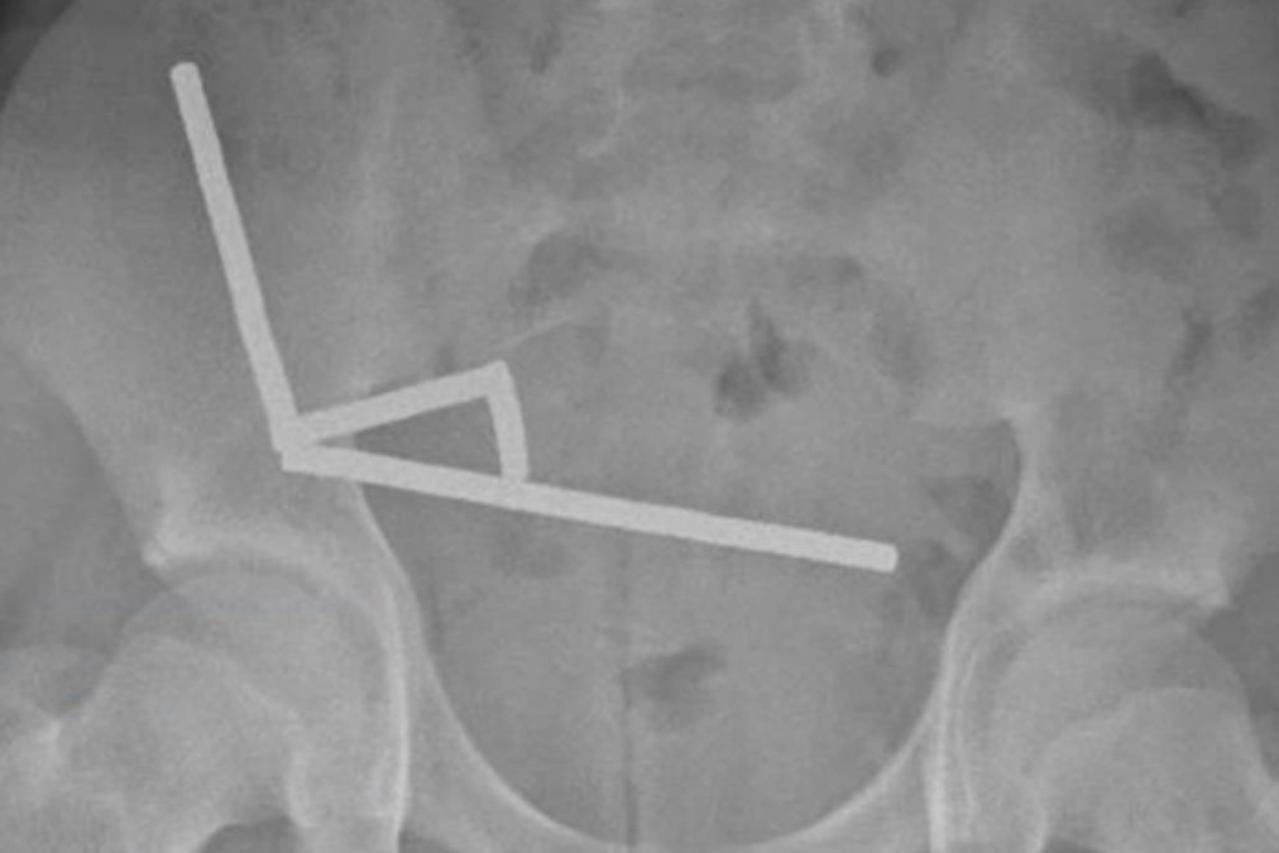

2 PROGUTAO MAGNETE Oglasio se Temu: Dječak primljen s jakim bolovima, liječnici nisu mogli vjerovati što su mu pronašli u crijevima Rendgenske snimke otkrile su četiri linearna lanca magneta u različitim dijelovima dječakovih crijeva